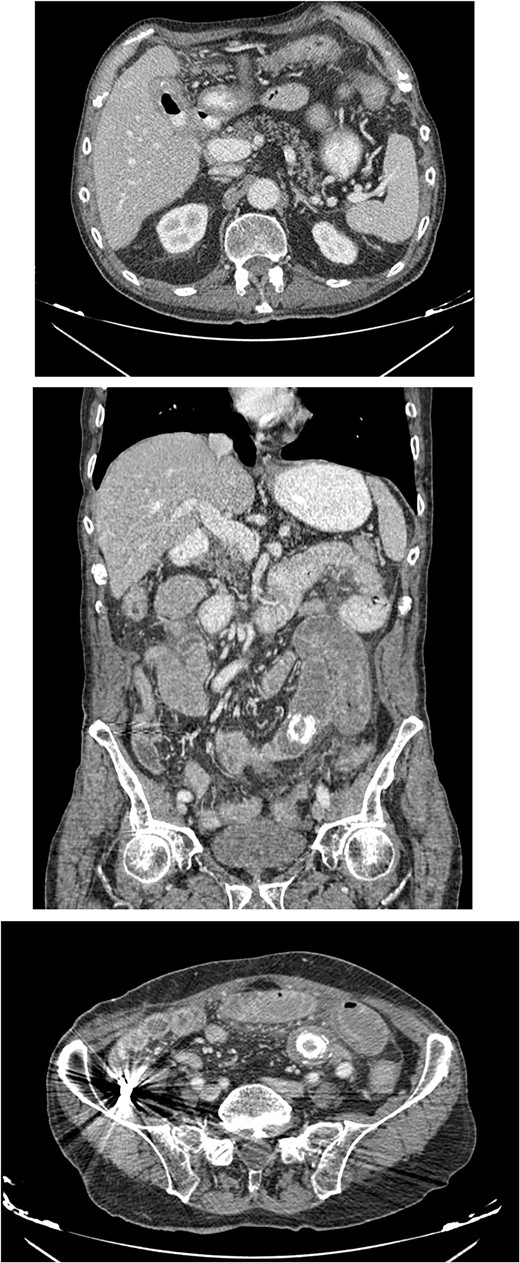

The patient was then admitted to the General Surgery department and treatment with broad-spectrum antibiotics (piperacillin/tazobactam and metronidazole) was initiated. On the second day of hospitalization, the patient underwent a repeat CT scan which indicated presence of air and oral contrast in the gallbladder, pneumobilia, swelling of the pylorus, and small bowel obstruction with the transition point being further into the ileum compared with the first CT scan (Fig. 1). Based on the comparison of the CT scan findings and past medical history of acute cholecystitis, gallstone ileus was established as the most possible diagnosis and the patient was led to the operating room.

CT images of the abdomen revealed small bowel obstruction due to gallstone and presence of air and oral contrast into the gallbladder.

An 80-year-old male presented to the emergency department complaining of intermittent abdominal pain, vomiting and intense nausea beginning 3 days prior. The patient reported a medical history of type 2 diabetes mellitus, hypertension and coronary artery disease. Upon arrival, he was afebrile (T: 37°C) and tachypneic (24 breaths/minute), the following vital signs were: heart rate 98 bpm, blood pressure 160/95 mmHg, oxygen saturation 96%. Examination of the abdomen revealed significant hypoactive bowel sounds and diffuse tenderness. Laboratory investigations revealed a white blood cell count of 8.190/mm3, hemoglobin of 15.9 g/dl, and elevated levels of C - reactive protein of 15.94 mg/dl (N < 0.5 mg/dl) whereas the rest of the laboratory parameters were within normal limits. The patient initially underwent plain chest and abdomen radiographs which revealed small bowel gas-fluid levels indicating intestinal obstruction and intravenous fluids resuscitation was initiated. A CT scan with IV and oral contrast which was later performed revealed gastric, duodenal and small bowel loops distension and swelling caused by a high attenuation mass within the intestinal lumen at the jejunum-ileum transition which was attributed to a gallstone. Α second possible gallstone of smaller diameter was located in jejunum loops, and a cholecysto-duodenal fistula, of air and oral contrast in the gallbladder, pneumobilia, and intraperitoneal fluid in Douglas’s pouch were also present (Fig. 3).

CT images with oral and IV contrast revealed presence of air and oral contrast in the gallbladder and small bowel obstruction caused by a mass in the jejunum–ileum transition attributed to a gallstone.